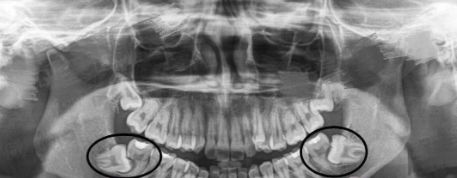

而且四颗智齿也不是都必然会长全,某些人的智齿可能只长1至2颗,有的智齿甚至长到一半就不再生长,这种情况称为智齿阻生,即阻生齿。

1.位置不正,常见于下颚智齿

智齿向前生长挤压到邻牙。此外,向后、向舌侧、向颊侧、甚至向下长也都可能产生危害。